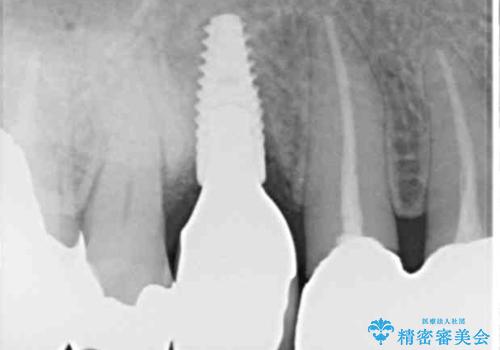

- 他院で抜歯が必要と診断され、インプラント治療を希望して来院された患者様です。

より審美的で、より機能的に優れた治療をご希望とのことであったので、ジルコニアカスタムアバットメントを用いたインプラント治療を行うこととしました。

ジルコニアカスタムアバットメントは、歯肉ラインに金属が見えにくいというだけでなく、クラウンを装着する土台の形が天然歯と近い形態となるため、清掃性が高く歯肉が腫れにくいというメリットがあります。

インプラントは、人工骨を用いた際の骨誘導能が比較的高いとさせるストローマン社のSLActiveを使用しました。